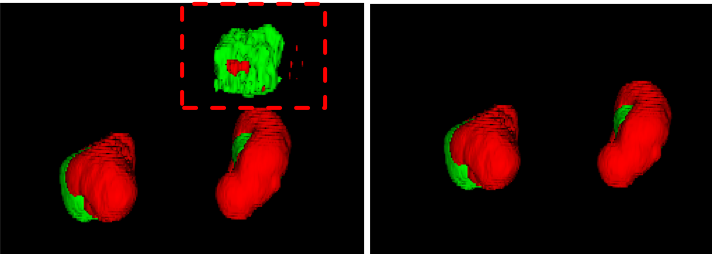

Some common human knowledge could help to enhance the performance further. For example, there are at most two kidneys in one patient and the tumor should be attached with kidney. So, we designed a simple connected-component based post processing method to remove the obviously mistaken predictions. The effect is shown as Fig.2.